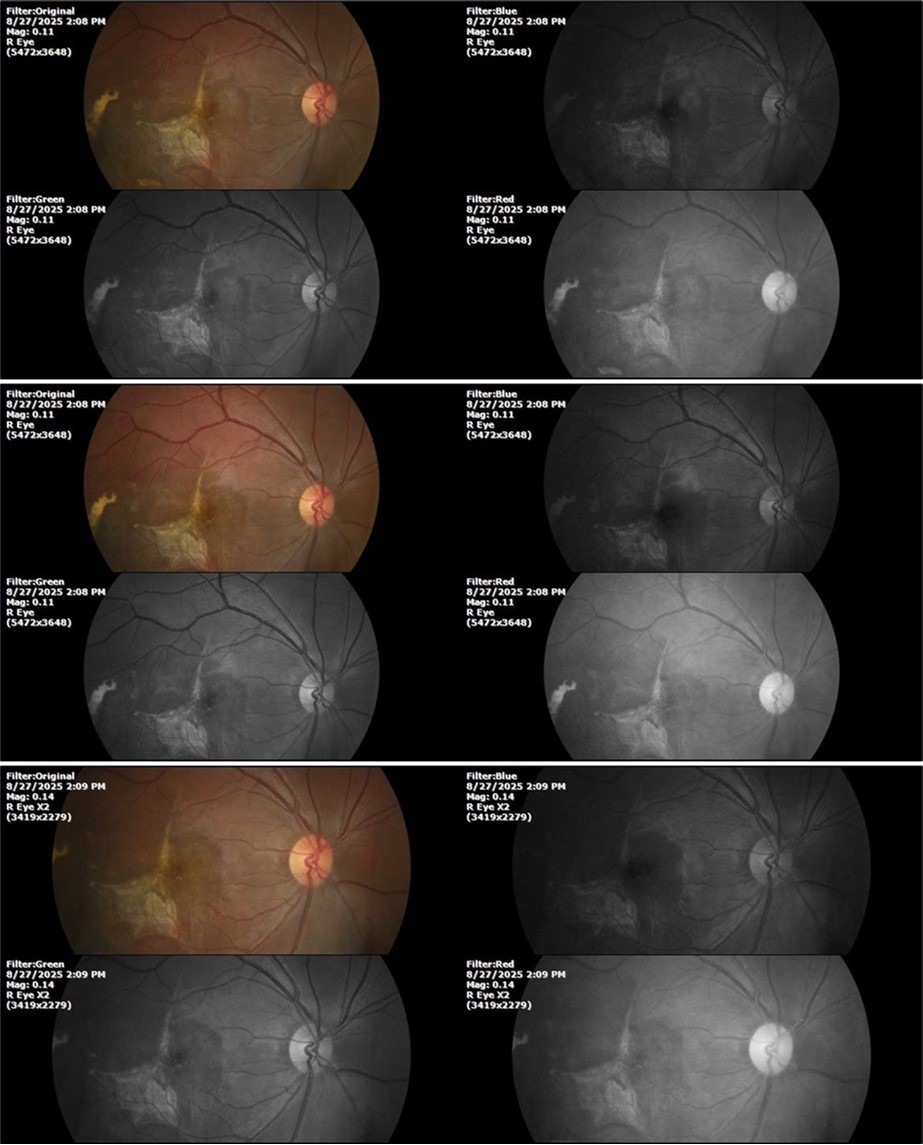

August 26, 2025

It's been fine, there's only a little veil that prevents it from seeing well completely, although it's very transparent (Figure 31, Figure 32, Figure 33, Figure 34, Figure 35, Figure 36).

Figure 33.The 3 previous photographs show that whitish mass has almost completely disappeared, and to date only a remnant remains on the left side of the photograph. The chorioretinal scar that is now observed corresponds to the area affected by the blunt trauma, which presumably caused rupture of Bruch's membrane. Fortunately, the macular region has recovered almost in its entirety, so the impairment in central vision was minimal.

The 3 previous photographs show that whitish mass has almost completely disappeared, and to date only a remnant remains on the left side of the photograph. The chorioretinal scar that is now                  observed corresponds to the area affected by the blunt trauma, which presumably caused rupture of Bruch's membrane. Fortunately, the macular region has recovered almost in its entirety, so the impairment in central vision was minimal.